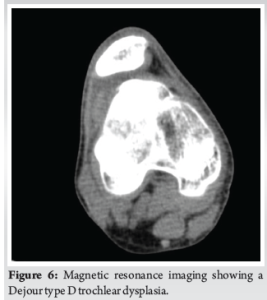

A 16-year-old boy presented to our outpatient department with a history of recurrent patellar dislocation in his right knee for the past 3 years. He also complained of a deformity of his right knee. On examination, his patella was grossly unstable, dislocating at about 30° of knee flexion (Fig. 1). Whole limb X-ray revealed a lateral mechanical axis deviation of 30 mm from the neutral (normal range – <10 mm) (Fig. 2). The opposite limb was normal. The Q angle of the right lower limb was measured to be 22°, which was abnormal (normal range 13–18°). The right knee was in valgus with a tibio-femoral angle of 15° (Fig. 3). The mechanical medial proximal tibial angle was 87.8° which was normal (normal range 85–90). However, the mechanical lateral distal femoral angle was 81°, which was abnormal (normal range 85–90) (Fig. 4 and 5). Hence, it was the distal femur that contributed to the genu valgum. The tibial tubercle–trochlear groove distance was 17 mm, which was normal (normal – under 20 mm), signifying that there was no rotational deformity. The Insall-Salvati ratio was 1.2, which was also normal (range – 0.8–1.2). Magnetic resonance imaging (MRI) revealed a Dejour Type D trochlea dysplasia (Fig. 6) with a trochlear depth of 1.2 mm (normal >3 mm) and a sulcus angle of 172 (normal <140). MRI also revealed an MPFL tear. The factors contributing to the patellar instability were recognized as the unacceptable genu valgum, trochlear dysplasia, and the MPFL tear. Considering that the patient had attained skeletal maturity and to avoid multiple procedures, a decision was made to correct all the anatomical abnormalities as a single procedure.